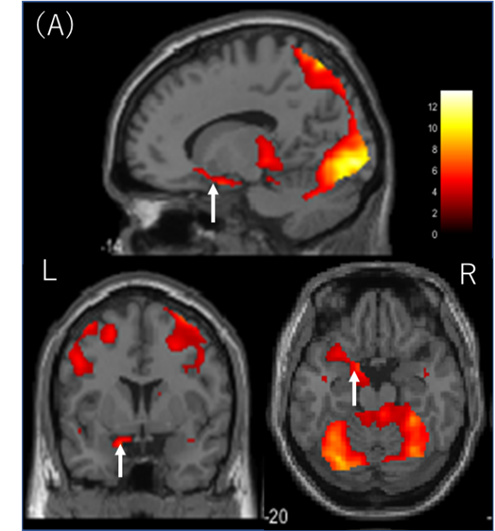

2.動画視聴中に特徴的であった側坐核の活性化の様子